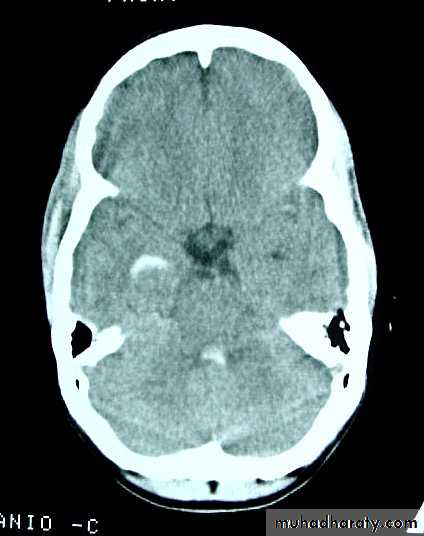

CT scans demonstrates contusions as small areas of haemorrhage in the cerebral parenchyma.

3. Cerebral Contusion

د.عبدالرحمن